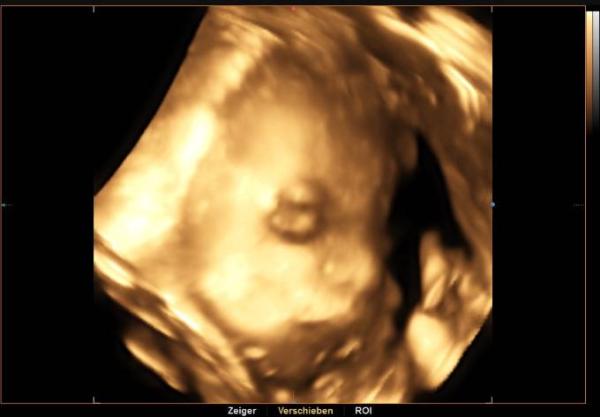

Hallo ihr Lieben. Heute sind wir schon in der 30. Woche angekommen Gestern hatten wir das dritte Screening und der kleinen Maus geht's prima. Sie wiegt schon ca. 1290 Gramm und ist gut entwickelt. Ich bin so froh, dass alles gut ist und ich bis jetzt ohne jegliche Beschwerden durch die Schwangerschaft gekommen bin. Es sind nurnoch knappe 2,5 Monate bis wir die Maus endlich in den armen halten dürfen. Wünsche euch allen einen schönen Abend

Hier noch ein Bildchen von gestern

Du hast aber ein schönes 3-D Bild. Ich bekomme auch aller 2 Wochen so eins, aber irgendwie sieht man immer nicht viel, mein Zwerg kuschelt immer mit der Plazenta. Du siehst auch super aus, schön schwanger.